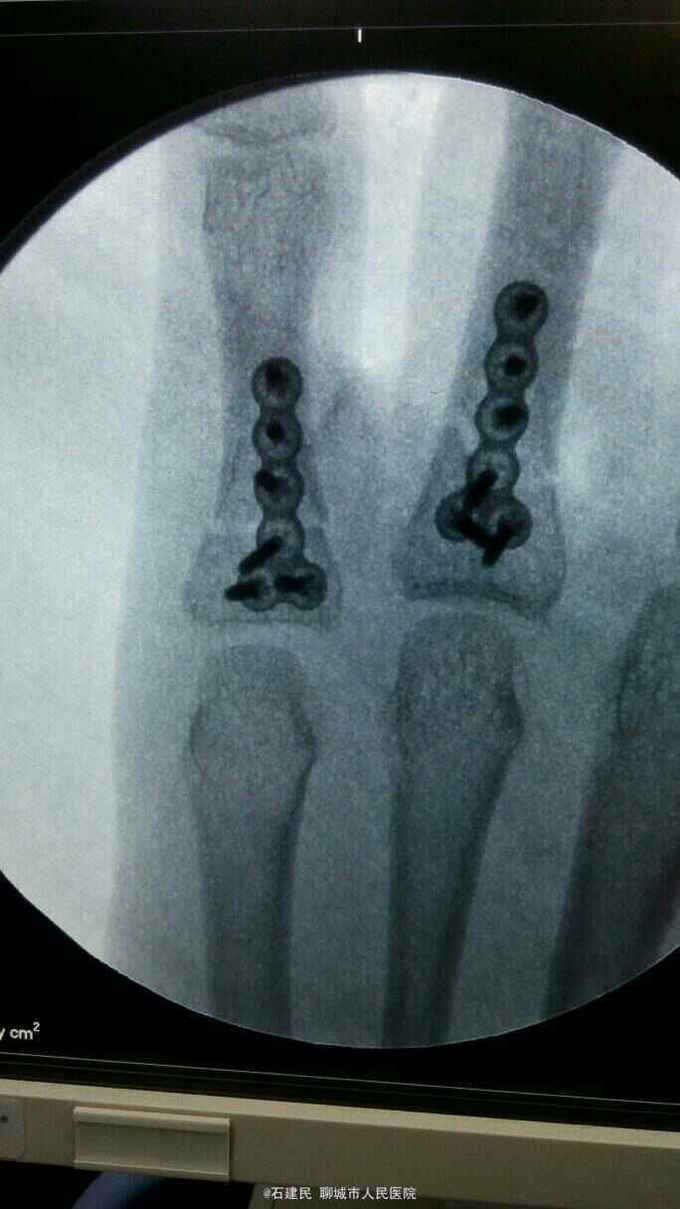

患者外伤致手部肿痛畸形,活动不能来我院就诊,行X线示环小指指骨骨折,收住院治疗。

查体可见神志清,精神正常,手背明显肿胀,畸形,环小指活动不能。

环小指指骨骨折,给予行切开复位内固定术,术中见环小指指骨近端骨折较短,给予行T型刚板固定。

患者骨折靠近掌骨基地部,单纯闭合复位很难固定,术后石膏保护3周,3周后去除石膏外固定主动活动锻炼。